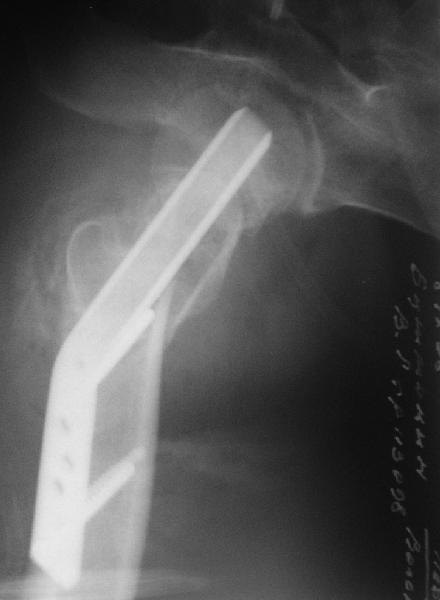

Приветствую всех. Спасибо за активное участие в обсуждении. Выбрали вариант с остеотомией.

Снимки в приложении.

Надеемся на днях поднять на костыли.

мое мнение может возраст еще позволить чем протезировать, я за остеотомию и синтез. только чем будешь фиксировать если первый вариант выберешь, мне кажется лучше ДХС, только я диафизарную часть пластины разгибаю под углом вальгуса, обычно заранее. недавно я тоже делал такой же случай, но там он был моложе. Ерсин. Астана